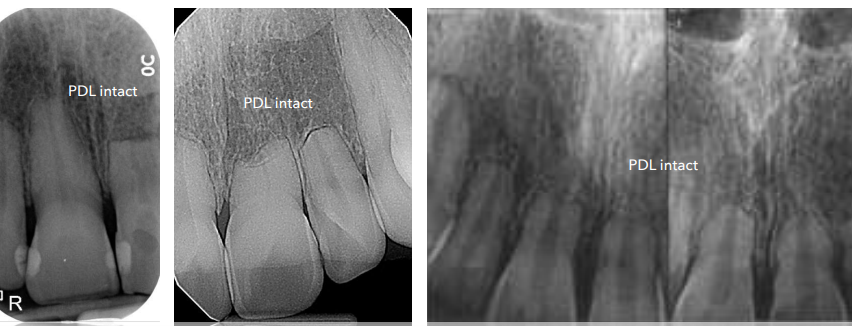

**PDL intact, no PA radiolucency **– no need for endo (used to preserve pulp, tx periradicular disease)

key feature of external surface resorption

A

PDL intact, no PA radiolucency

no need for endo